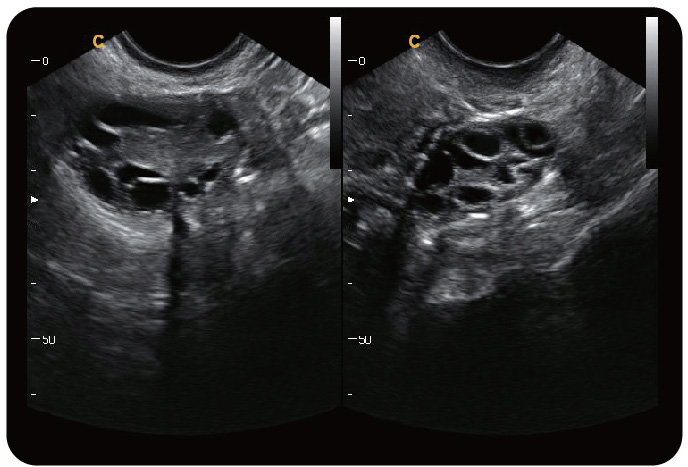

卵巢,2B模式